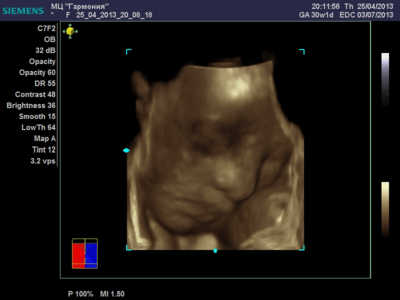

А я вчера на 3Д УЗИ ходила. Моя звезда закрывалась в еми 4мя конечностями. Просто пополам сложилась и спала себе сладко. УЗИстка провела со мной час, кое-как расшевелили маленькую, но ручка была постоянно на мордашке и засыпала она почти сразу снова. Я и на мяче прыгала и живот трясла. В конце более-менее фото вышли, но качество меня не порадовало. Возможно фри оф чардж еще раз переделают. Со средней фотки были отличного качества, а эти сплошное разочарование. Вот тут что-то более-менее еще. Главное пальчик оттопырила так смешно, мол минуточку. Вообще немного жутковатые фотки..хаха

Еще одна, качество ужасное..

ANGEL*ina, у вас качество очень даже неплохое. GE машины очень хорошие. У моей врачихи такая. Мы сегодня ездили на повторное 3Д узи. Повезло немного больше чем неделю назад. У малыша явно шило в попе. Он кувыркался. За 20 минут несколько раз поменял позицию полностью, и под конец вообще отвернулся. Корд тоже постоянно перед его личиком болтался, да и руками он себя частенько закрывал. Качество фотографий ужасней не придумать.

Вот, пожалуй, самая лучшая фотография.